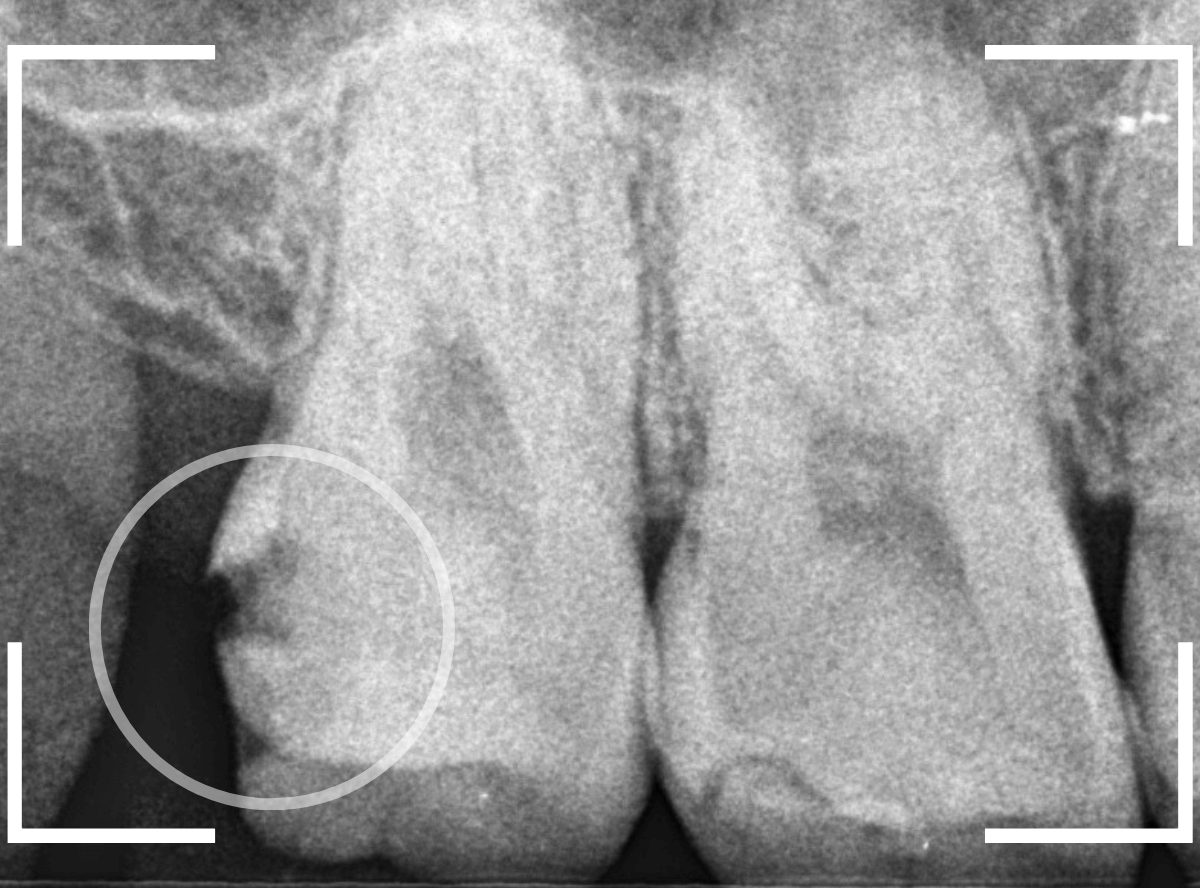

レントゲン写真です。

レジンの下が虫歯になっているのがわかります。

レントゲン写真で確認します。

青い線が歯の神経、赤い線が虫歯です。

おやしらずがあった際にはわかりづらかったですが、歯の後ろ側のおやしらずが重なっていたところが虫歯になっているのがわかります。

おやしらずが原因で、このように手前の歯が虫歯になってしまう事が多いために、抜歯を勧められる事が多いのです。

そして、虫歯の部分におやしらずが被さっていたために、しみる症状などを感じなかったのです。